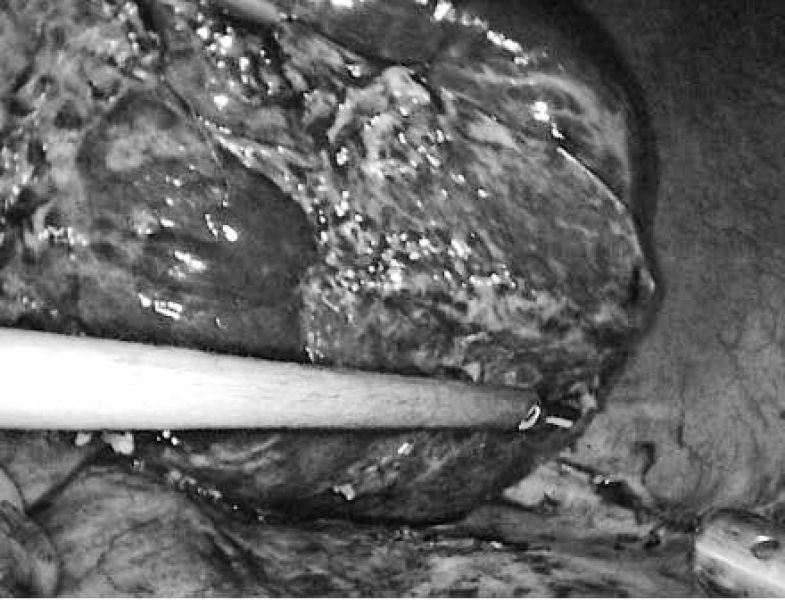

腹腔镜下病变肝脏的显露